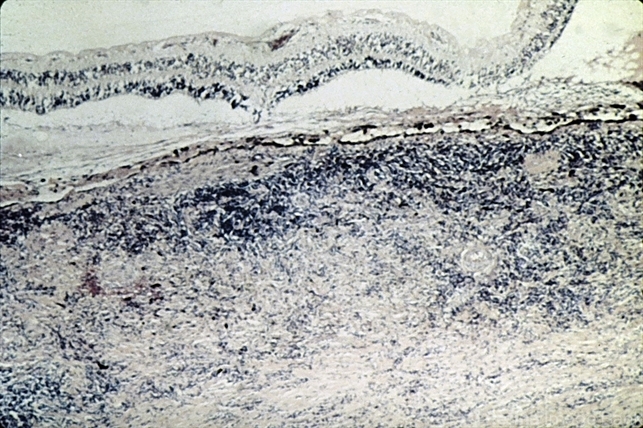

- scleritis, sclera

- Scleritis showing marked granulomatous inflammation of the sclera.